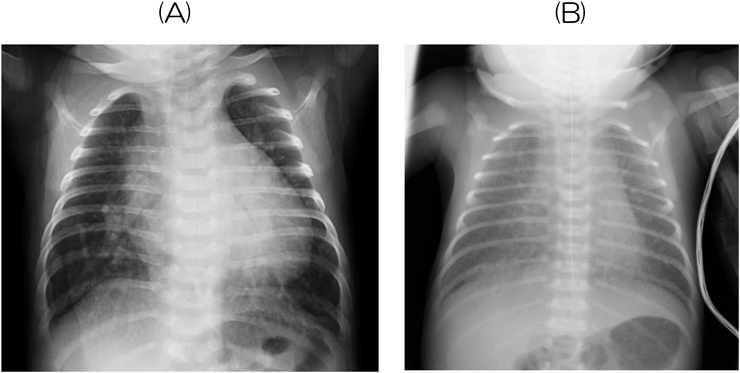

胸部レントゲンでは,心胸郭比や肺血管陰影を評価する(Fig. 6).心陰影のみならず,気管分岐角(左房拡大で開大)などにも注目する.新生児・乳児ではしばしば吸気不充分な撮像条件となり,正確な評価が難しくなる.心電図は一般的に行われており非常に多くの情報を得ることができる.正常値が年齢により異なることに留意する18).心臓超音波検査はベッドサイドで簡便に施行でき,最も診断能力が高いツールで,解剖学的診断から心機能・血行動態評価まで様々な情報が得られる.しかし,症例によっては適切な画像の描出が困難であるなど弱点もある.また,基本的には非侵襲的な検査であるが,新生児では圧迫による呼吸障害や長時間の検査に伴う低体温などに留意しないと,時に侵襲的検査になってしまう.あくまでモダリティの1つであり,理学所見や他の検査所見と総合的に評価し判断することが重要である.

Fig. 6 Typical findings on chest radiography

(A) Increased pulmonary blood flow; A 1-month-old boy with ventricular septal defect. It shows cardiomegaly (the cardiothoracic ratio 64%), and left mainstem bronchus elevation, suggesting left atrial enlargement. The enlarged pulmonary arteries extend into the lateral lung field, and the external diameter of the pulmonary artery is wider than the internal diameter of the trachea. (B) Pulmonary venous congestion; A 3-day-old girl with total anomalous pulmonary venous return. It shows the hazy and indistinct margin of the pulmonary vasculature. The margin of the cardiac border is also unclear, and there is no cardiomegaly.